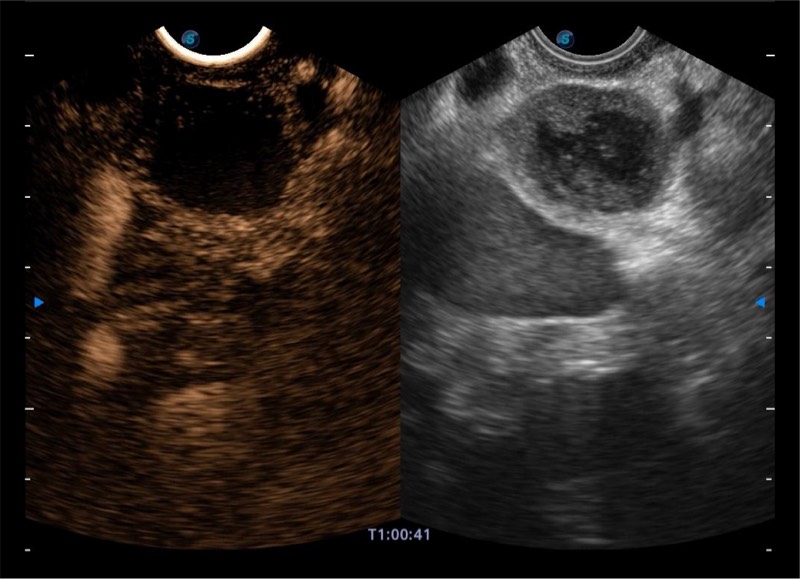

基于二十年的超声技术积累,乐玩lewin国际提供了最新一代的独立超声主机,在提供高质量图像的同时满足多学科使用。具备常见多普勒技术并提供弹性成像、声学造影等高端影像技术。新一代传感器具有更强的抗干扰能力并减少图像伪影。

搭载百万级CMOS成像技术

及自主研发凸阵换能器,

可呈现优质的内镜和超声画面